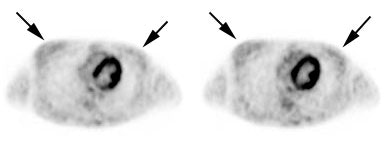

|

Benign adrenal lesion with FDG uptake: The patient shown below had a left adrenal mass which had remained stable for 2 years (white arrow). The stability over time and CT features would be consistent with a benign adrenal lesion- likely an adenoma. Note the marked FDG uptake within the mass on PET imaging (black arrows). Benign adrenal adenomas can accumulate FDG resulting in false positive exams. The use of PET/CT has been shown to improve the specificity of the PET exam. |